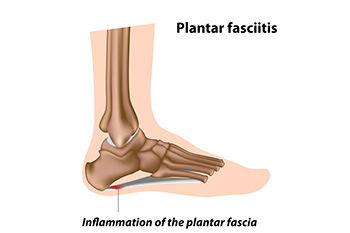

What Can Cause Plantar Fasciitis?

The plantar fascia is a thick band of tissue that connects the heel to the toes. Plantar fasciitis, an inflammation of this tissue, can stem from various biomechanical factors. Problems like an abnormal lower leg structure, limited ankle movement, and inward or outward heel or foot angles can strain the plantar fascia. These abnormalities can alter foot mechanics, leading to excessive tension and micro-tears in the fascia. Symptoms include sharp heel pain, especially after prolonged periods of standing or walking, which tends to improve with rest but worsens upon resuming activity. Early morning stiffness and tenderness in the heel or arch are also common. Addressing these biomechanical issues through proper footwear, orthotics, stretching exercises, and avoiding excessive strain on the feet can help to manage symptoms and prevent recurrence of this ailment. If you have been afflicted by plantar fasciitis, it is suggested that you confer with a podiatrist who can offer you various effective treatment methods.

What Is Plantar Fasciitis?

Plantar fasciitis is one of the most common causes of heel pain. The plantar fascia is a ligament that connects your heel to the front of your foot. When this ligament becomes inflamed, plantar fasciitis is the result. If you have plantar fasciitis you will have a stabbing pain that usually occurs with your first steps in the morning. As the day progresses and you walk around more, this pain will start to disappear, but it will return after long periods of standing or sitting.